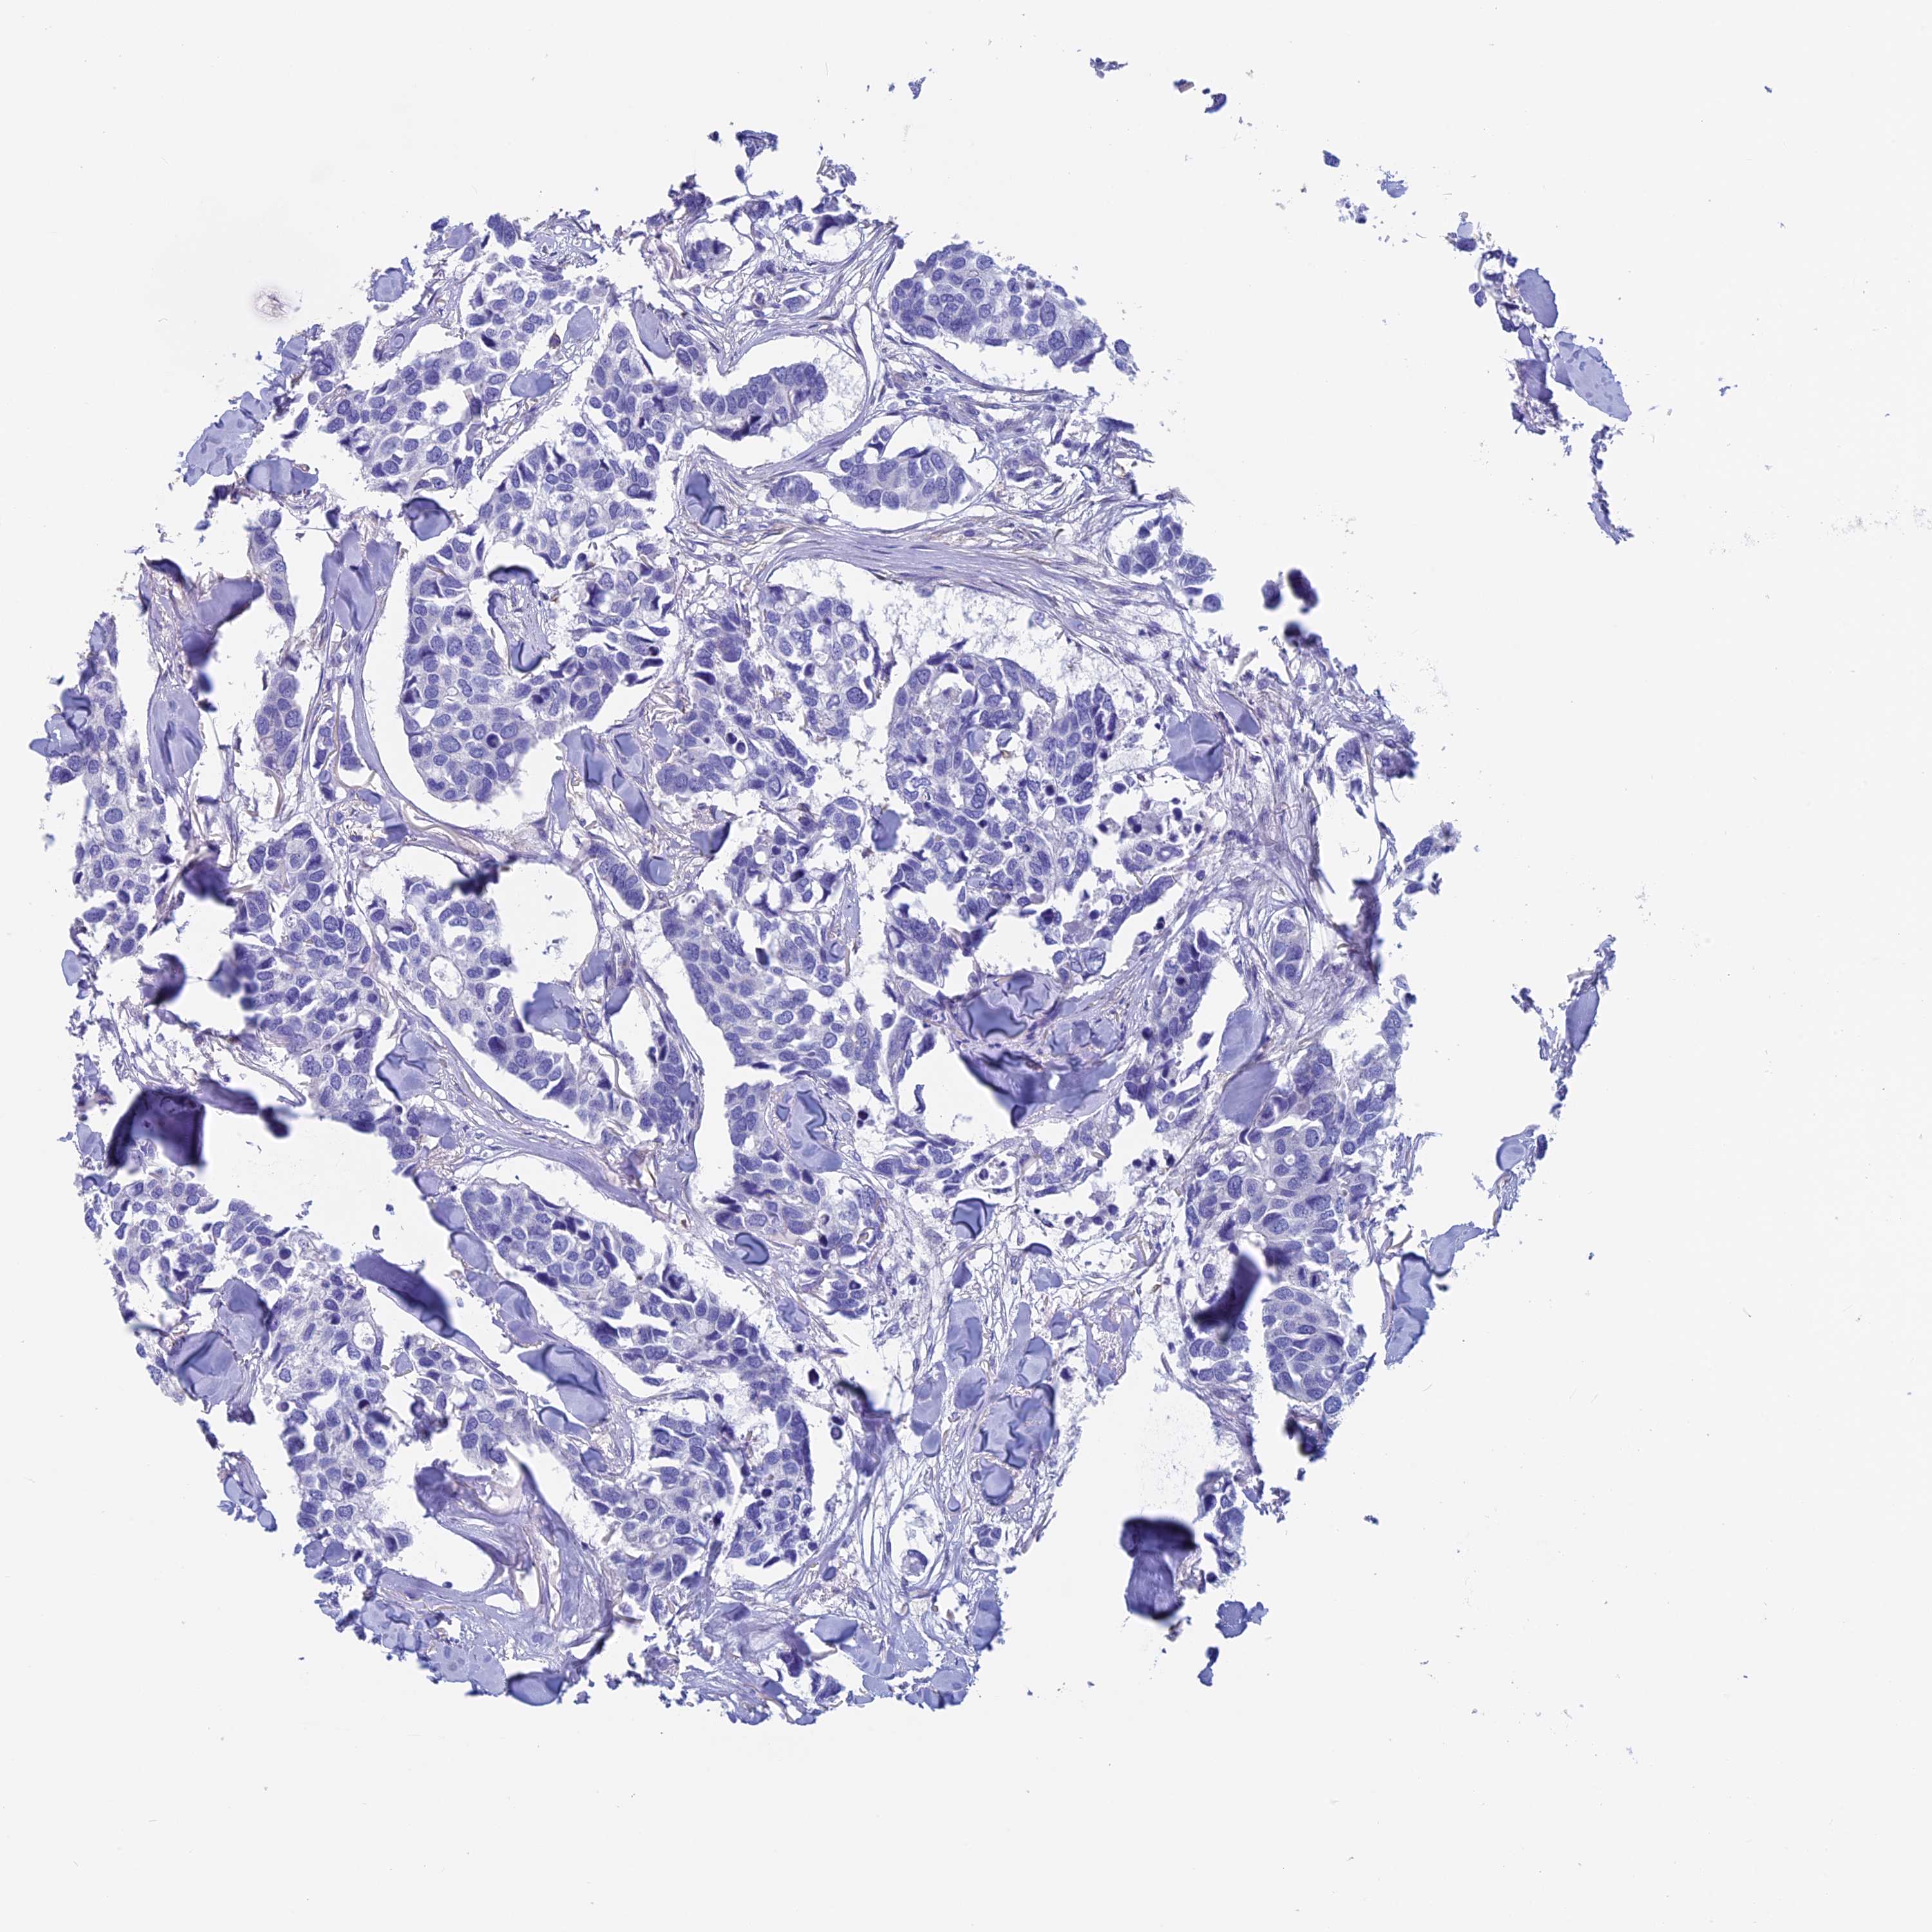

Breast cancer

Human cancer